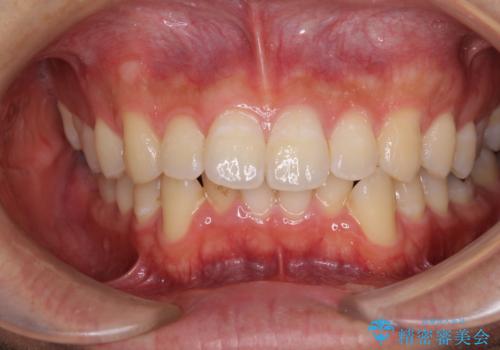

口が少し閉じにくい インビザラインによる非抜歯矯正

- 口元の突出感を治したいとのことで来院された患者様です。

上下顎ともにIPR(歯と歯の間を削る)と歯列全体の拡大によって口元が引っ込むように設計し、インビザラインにより治療を行うこととしました。

抜歯をして口元を下げなければならないほど出っ歯ではなかったため、少しずつ治療ゴールを変更しながら仕上げていきました。

気になっていた前歯の飛び出した印象は、最終的にはスッキリと引っ込み、大変満足していただきました。